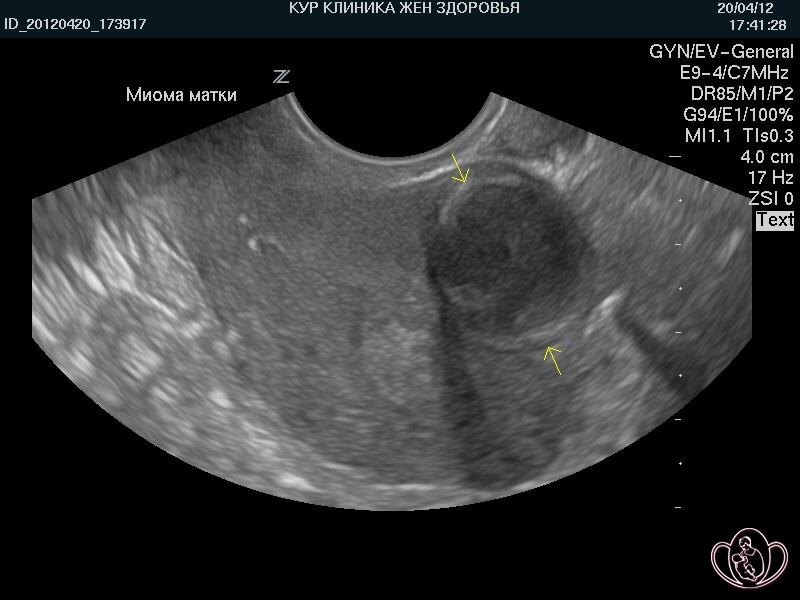

У женщины обильные болезненные месячные со сгустками, анемия (слабость, головокружение), давление на мочевой пузырь. На УЗИ - подслизистая миома, и вместо комплексного лечения ей предлагают понаблюдать или назначают лишь обезболивающие и препараты железа.

Миома растет, деформирует полость матки, нарушает кровоснабжение. Анемия истощает организм. Обезболивающие не решают проблему, а лишь маскируют ее, позволяя болезни прогрессировать до таких размеров, когда щадящее лечение станет невозможным.

Рост миомы в постменопаузе — ТРЕВОЖНЫЙ знак, требующий немедленного исключения злокачественного процесса (лейкосаркомы). Поэтому нельзя прекращать наблюдение за образованием. Делайте контрольное УЗИ раз в 6-12 месяцев обязательно.

Некоторые миомы (субмукозные, деформирующие полость) значительно снижают шансы на зачатие и вынашивание. Беременеть, не решив проблему может быть опасно из-за риска осложнений (выкидыш, отслойка плаценты).